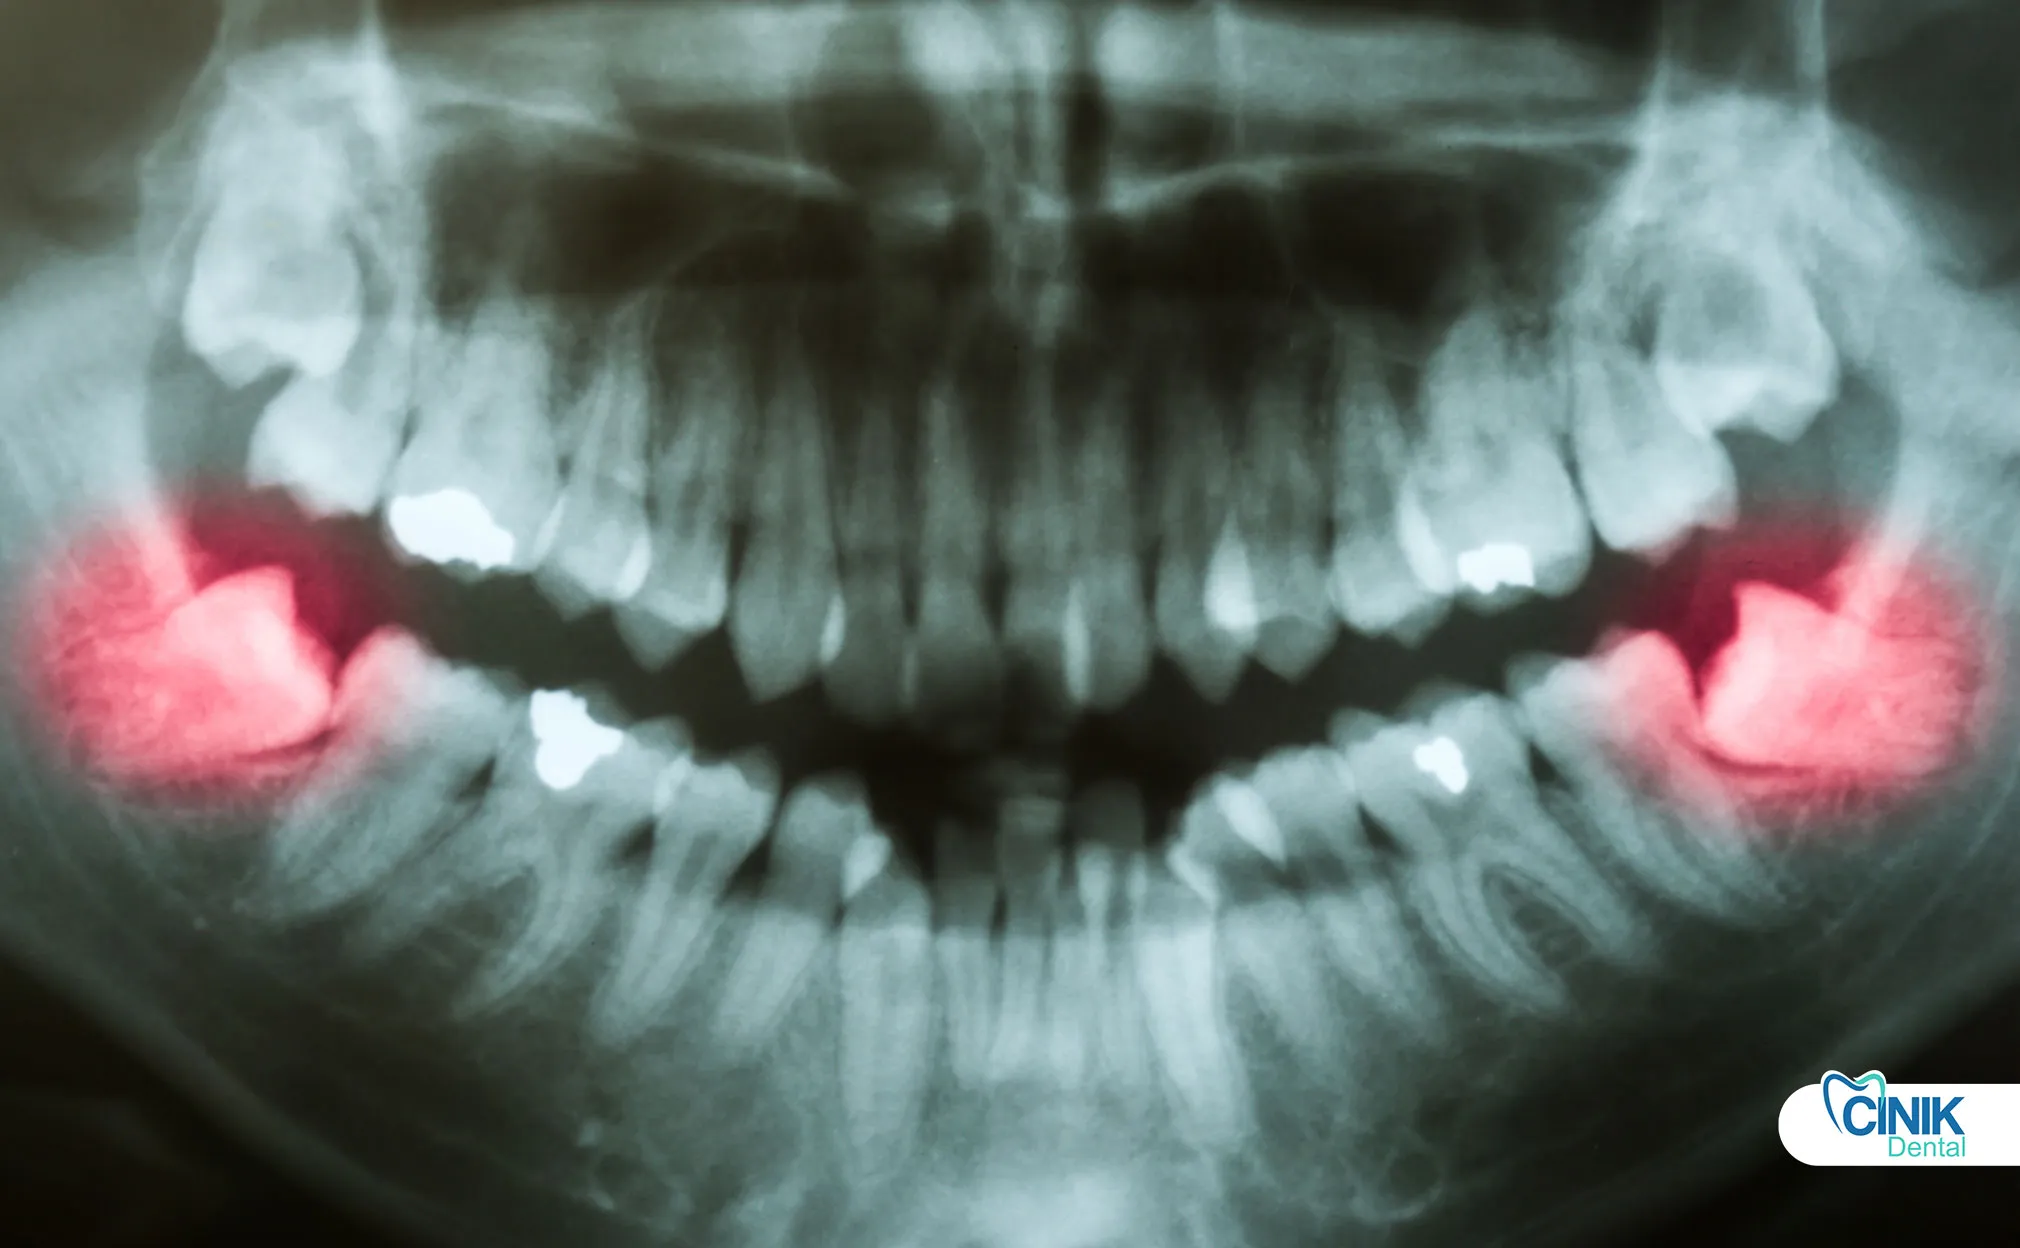

Radiographic imaging provides essential anatomical information:

Panoramic radiography (OPG) serves as the standard initial screening tool. This two-dimensional image reveals:

Tooth angulation and impaction depth

Root morphology and curvature

Relationship to adjacent teeth

Approximate nerve canal positioning